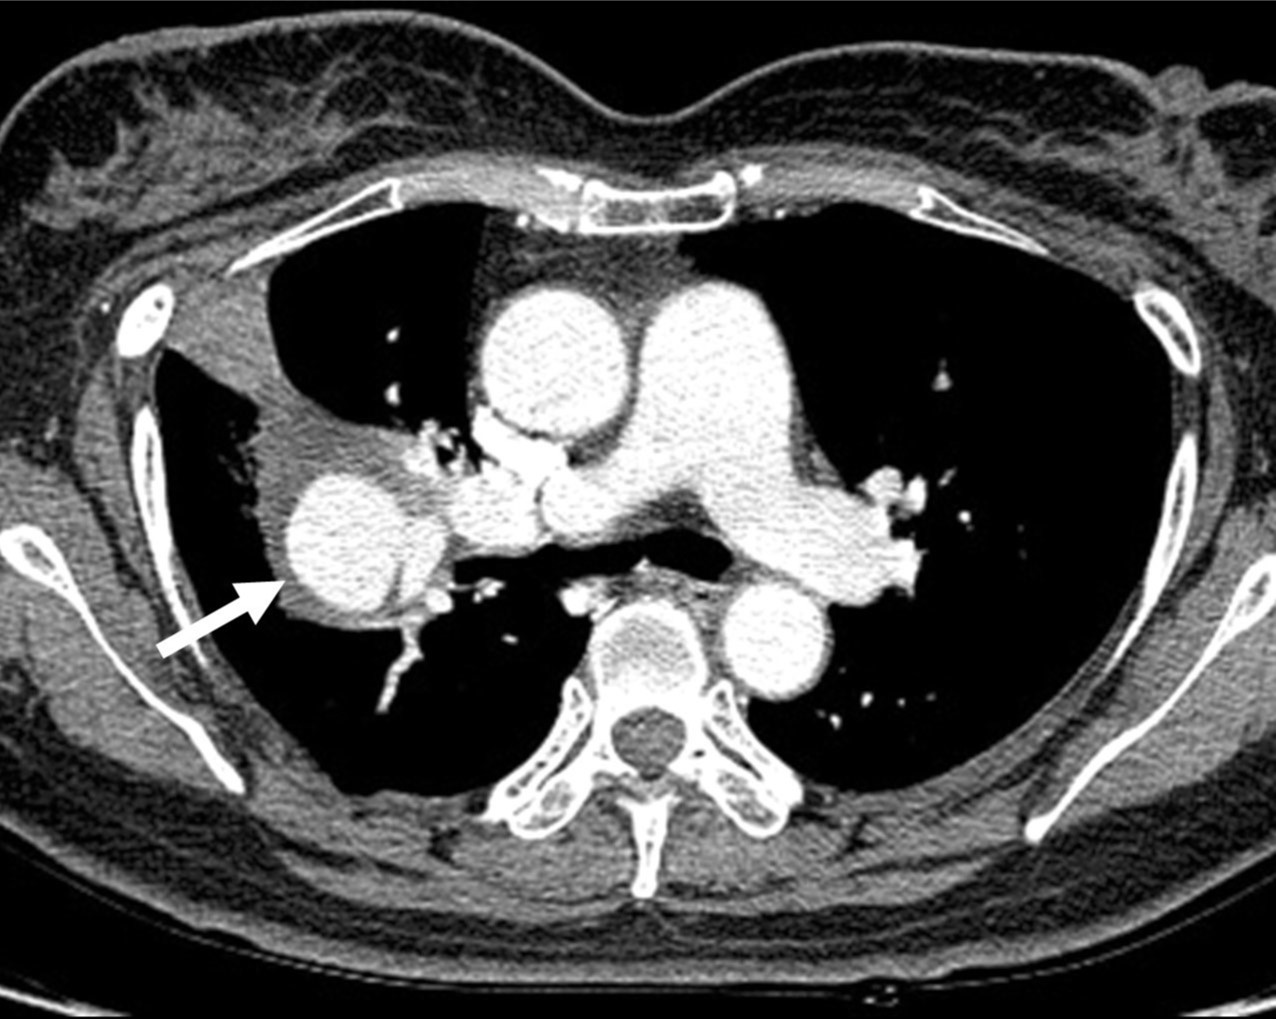

근위부와 연결되는 34mm 크기의 가성동맥류가 관찰되었고, 이 가성동맥류는 과거에 존재하던 cavitary metastatic mass내부를 가득 채우면서 주변으로 혈종으로 추정되는 soft tissue attenuation에 의해 둘러싸여 있었음(Fig. 1).

Fig. 1. A

Fig. 1A, B. The axial (A) and coronal (B) images of chest CT scan demonstrate a pseudoaneurysm (arrows) in the right lower lobe, connected to the proximal part of the right lower pulmonary artery.